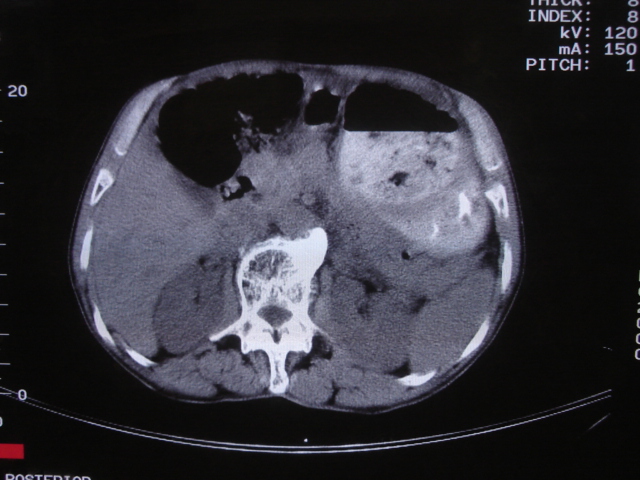

以下是引用深泽交通医院在2008-7-17 12:39:00的发言:[br]胃下垂;胃窦占位